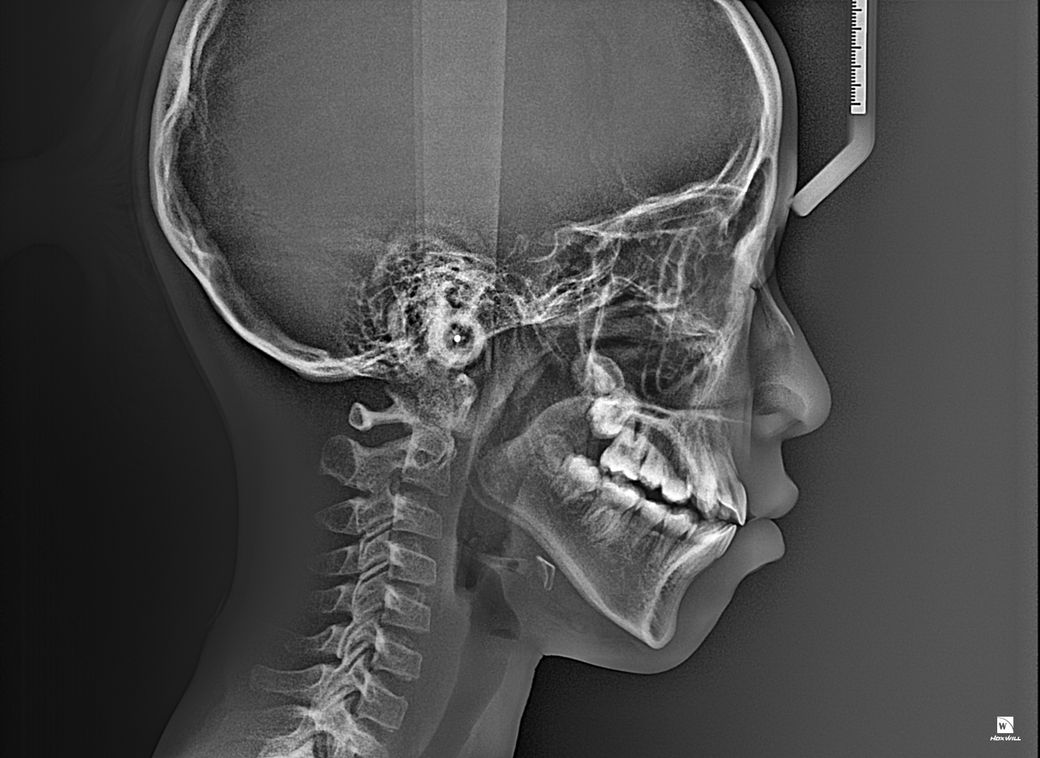

중1 여자 아이 교정진단 부탁드립니다.

앵글씨 몇급인지 궁금합니다.

의사 선생님마다 소견이 다르셔서 혼란 스럽네요.중1 여자 아이구요.시기적으로 지금 교정을 시작하기에 적절한지 궁금합니다.

앵글 2급 부정교합이며, 지금 교정하는 것이 좋을 것으로 보입니다. 더 늦어지면 교정이 까다로워 질 수도 있습니다. 지금 현재도 쉬운 케이스는 아닙니다.

앵글씨 부정교합측면에서 보면 1급인거 같고 치열이 좋지 않아서 중학교 1학년이면 교정을 시작하셔도 괜찮을 시기인거 같습니다.